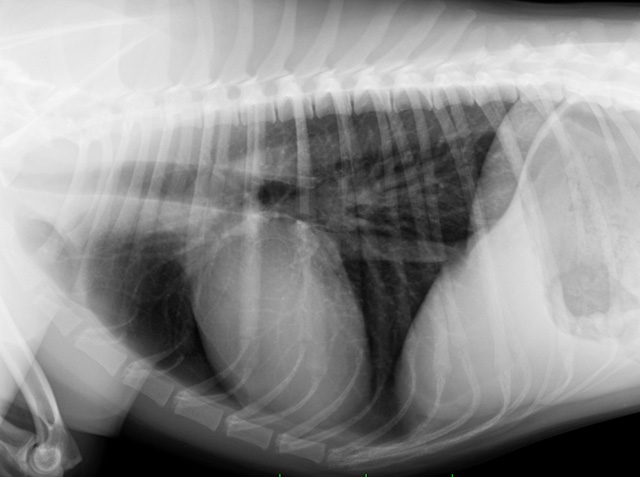

避妊・去勢手術は、多くの動物たちが一生に一度経験する大切な手術です。ESSE動物病院 宝塚では、吹田本院で培った高度な外科実績に基づき、外科認定医が監修する「安全性を最優先した手術」を提供しています。

統計的に、避妊手術により一部の免疫疾患リスクが1.6倍になるという報告もありますが、一方で命に関わる「子宮蓄膿症」のリスクは0.04倍(25分の1)にまで激減します。当院では、「将来的な重大疾患を防ぐメリット」の方が圧倒的に大きいと考えています。